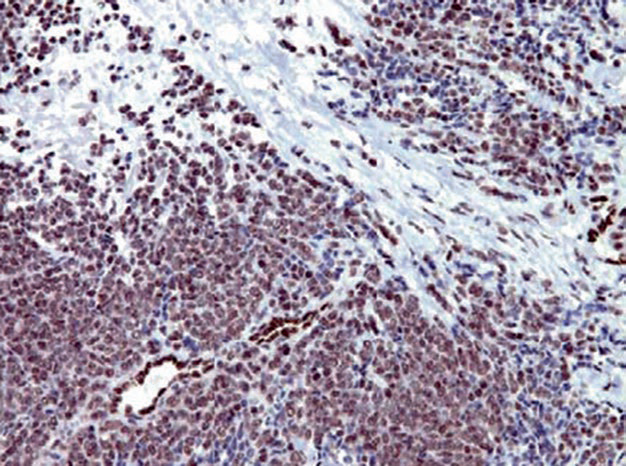

图片

Figure 2. Ewing sarcoma, FLI-1 shows strong positive expression in the nucleus; note that the vascular endothelial cells in the image can serve as an internal control.

It should be noted that FLI-1 expression is not limited to PNET family tumors; for example, this marker is also a good marker for vascular tumors, and some malignant melanomas (mainly aggressive subtypes) can also express it. One pitfall in the application of FLI-1 is that blasts in acute lymphoblastic leukemia express this marker, and since CD99 is also positive and the morphology resembles PNET, misdiagnosis is easy. In such cases, adding TdT is crucial for definitive diagnosis.